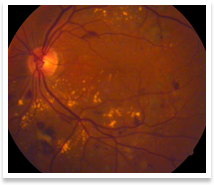

Diabetic Retinopathy

Diabetic retinopathy refers to the adverse effects of diabetes mellitus(raised blood sugar levels) on the retina(the back portion) of the eye. This can happen to patients with both type 1 diabetes (insulin dependent) or type 2 diabetes(which may or may not be insulin dependent).

A diagnosis of diabetic retinopathy can be established by indirect ophthalmoscopy (a technique used to visualize the retina or back portion of the eye). Special investigations, such as fundus fluorescein angiography, ocular coherence tomography scans(OCT) or ultrasonography(B-scan) may be required to plan treatment, dependent upon the stage of the disease.